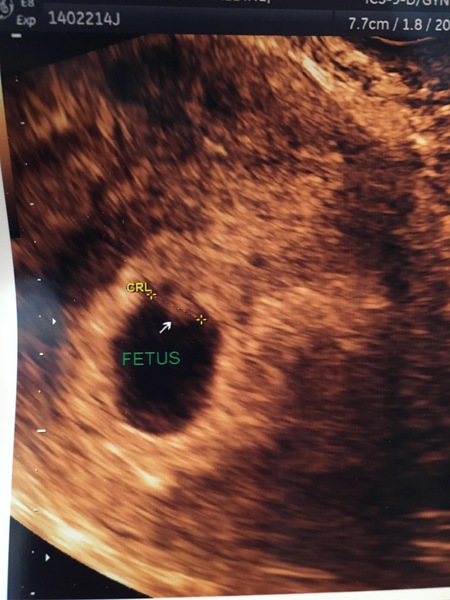

I've just had my scan, measuring a couple of days behind (6w+5) but saw a heartbeat which was nice. Dr confirmed a "viable intrauterine pregnancy" so I'm guessing that means so far so good?!

What a fab scan picture for so early. It's always reassuring to see your little blob alive and heart beating on the screen.

Thank you both Smile it's amazing you can see anything considering the little bean is only 7mm in length! So tiny! It's nice to see but in a way I wish I'd waited til 8 weeks as you definitely see more of a defined blob by then. Got 5 weeks to wait for the 12 week scan now!